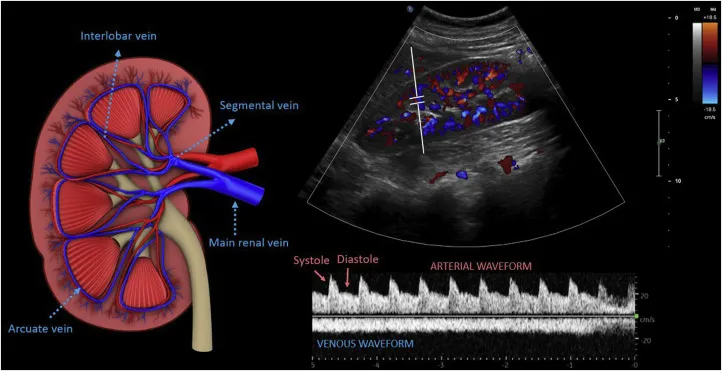

- Principle: Detects flow via Doppler shift ($f_D$) from moving RBCs. $f_D = (2 \cdot f_t \cdot v \cdot \cos\theta) / c$.

- Doppler Angle ($\theta$): Angle (beam to flow). Optimal 0°, acceptable <60°. At 90°, no shift.

- Color Doppler: Mean velocity & direction. 📌 BART: Blue Away, Red Towards.

- Power Doppler: Slow flow detection, less angle-dependent.

- Spectral Display: Velocity vs. time. Window: laminar; broadening: turbulent.

⭐ For accurate velocity, maintain Doppler angle <60°. At 90°, flow appears absent.